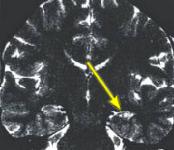

Fig.1 Fig.2 Fig.3

MRI FINDINGS: MRI detects mesial temporal sclerosis by demonstrating size asymmetry and abnormal signal within the atrophied hippocampus. Thin-section, high-resolution oblique coronal MR images are best for detecting these abnormalities, which can be subtle. Heavily T1-weighted images (Fig. 1) are best for detecting size asymmetry of the hippocampal gyri, while T2-weighted images (Fig. 3) and particularly FLAIR (fluid attenuated inversion recovery) images are most sensitive for detecting signal abnormalities (Fig. 2). The above images demonstrate left hippocampal atrophy and mesial temporal sclerosis (arrows).